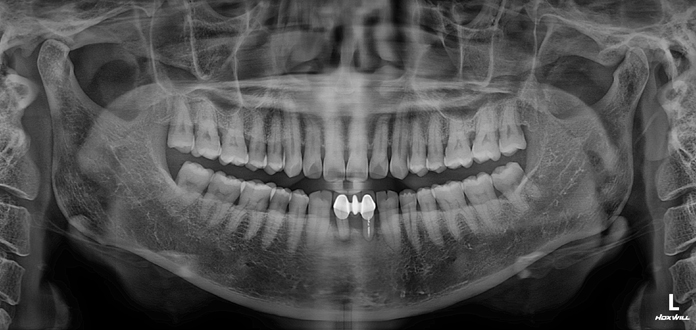

Before

After